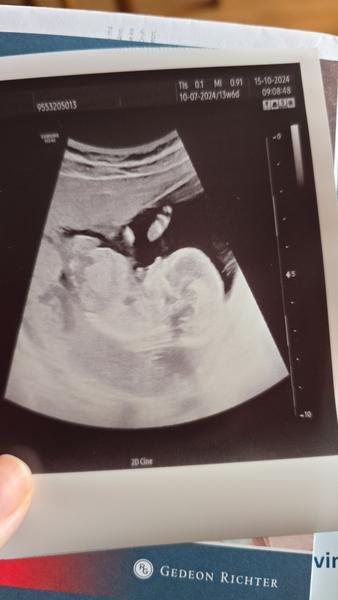

Jak odhadnout pohlaví z ultrazvuku ve 13. týdnu?

Vím, že je ještě brzo, ale zvědavost je prostě silná a když se koukám na ultrazvuk (ze 13 a 14 týdne), tak nic nemůžu poznat. 😅 Vidíte tam něco? Podle doktora na 70% kluk, ale moje intuice říká holka. U toho druhého mě to připomíná kluka, ale nejsou to jen nožičky?

Promiň ale z tohto to tedy já osobně nepoznávám. Má tam nožičky 🙂